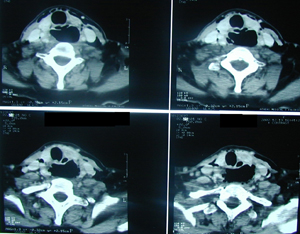

Εικόνα 2α-δ

Αξονική τομογραφία θώρακος σε διαφορετικά επίπεδα. Αναδεικνύει τα ίδια ευρήματα με την απλή ακτινογραφία και θέτει την διάγνωση της ρήξης της τραχηλικής μοίρας του οισοφάγου με εικόνα εμπυήματος του δεξιού ημιθωρακίου και εικόνα μεσοθωρακίτιδας με υδραερικό επίπεδο τόσο στο μεσοθωράκιο όσο και στον τράχηλο.